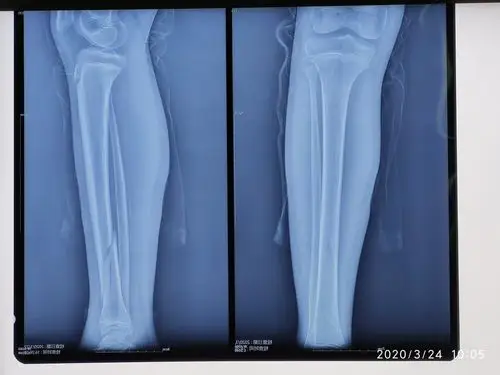

儿童胫骨远端骨骺损伤(近期三例)

左胫骨骨骺骨折